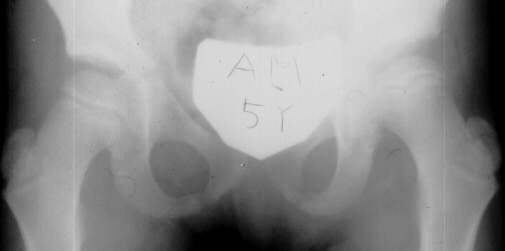

A ten year old female presented with a left hip dislocation. She was born by Cesarean-section because of slow progression of labor. The child was not breech and was noted to have a dislocatable hip at birth. There was a negative family history of DDH. An X-ray prior to application of the brace showed the dislocation of the hip. The patient was first seen at AIDI on 9th day. Abduction of the right hip was 80 degrees but left was only 60 degrees. There was a positive Galeazzi sign with the left hip being shorter than the right. X-rays showed a left hip dislocation and right hip subluxation . A Pavlik harness was applied. After two months, the right hip improved but the left hip was still dislocatable. For this, home traction was started. Even after 2 months, the left hip did not reduce. Therefore, an arthrogram, adductor tenotomy and closed reduction was done at 4 months of age. Single hip spica was applied with the hip in 40 abduction and 100 flexion. Eight weeks later an arthrogram was performed and the cast was reapplied with the hip in 35 degrees abduction and 100 degrees flexion.

Four months later, the spica cast was removed and an Atlanta brace was applied. X-rays showed avascular necrosis at ten months of age . At two years of age, the ossification of the left nucleus was still delayed. The leg lengths were equal and the range of motion of the hip was full.

The progression of the hip is documented by x-rays taken at 1 year of age, 2 years of age, 3 years of

age, 5 years of age, 7 years of age, then at ten years of age, early closure of the lateral portion of proximal growth plate observed. Coxa valga was also observed.